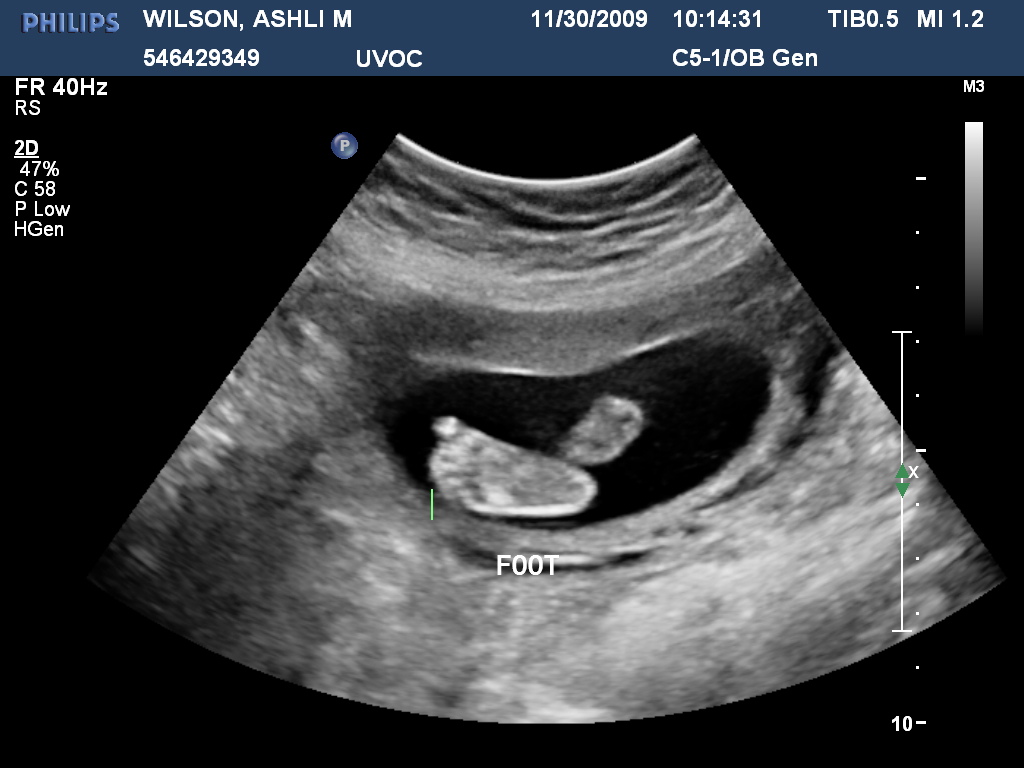

Her legs all stretched out.